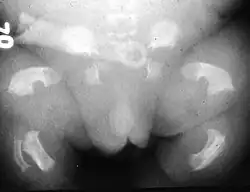

| Radiogram of a baby born with thanatophoric dwarfism | |

Thanatophoric dysplasia is a severe skeletal disorder characterized by a disproportionately small ribcage, extremely short limbs and folds of extra skin on the arms and legs.

Infants with this condition have disproportionately short arms and legs with extra folds of skin. Other signs of the disorder include a narrow chest, small ribs, underdeveloped lungs, and an enlarged head with a large forehead and prominent, wide-spaced eyes. Thanatophoric dysplasia is a lethal skeletal dysplasia divided into two subtypes. Type I is characterized by extreme rhizomelia, bowed long bones, narrow thorax, a relatively large head, normal trunk length and absent cloverleaf skull. The spine shows platyspondyly, the cranium has a short base, and, frequently, the foramen magnum is decreased in size. The forehead is prominent, and hypertelorism and a saddle nose may be present. Hands and feet are normal, but fingers are short. Type II is characterized by short, straight long bones and cloverleaf skull.[1] It presents with typical telephone-handle shaped long bones and H-shaped vertebrae.

Infants with type 1 thanatophoric dysplasia also have curved thigh bones, flattened bones of the spine (platyspondyly) and shortened thoracic ribs. Note: Prenatal ultra-sound images of the ribs sometimes appear asymmetrical when in fact they are not. In certain cases, this has caused a misdiagnosis of osteogenesis imperfecta (OI) type II.